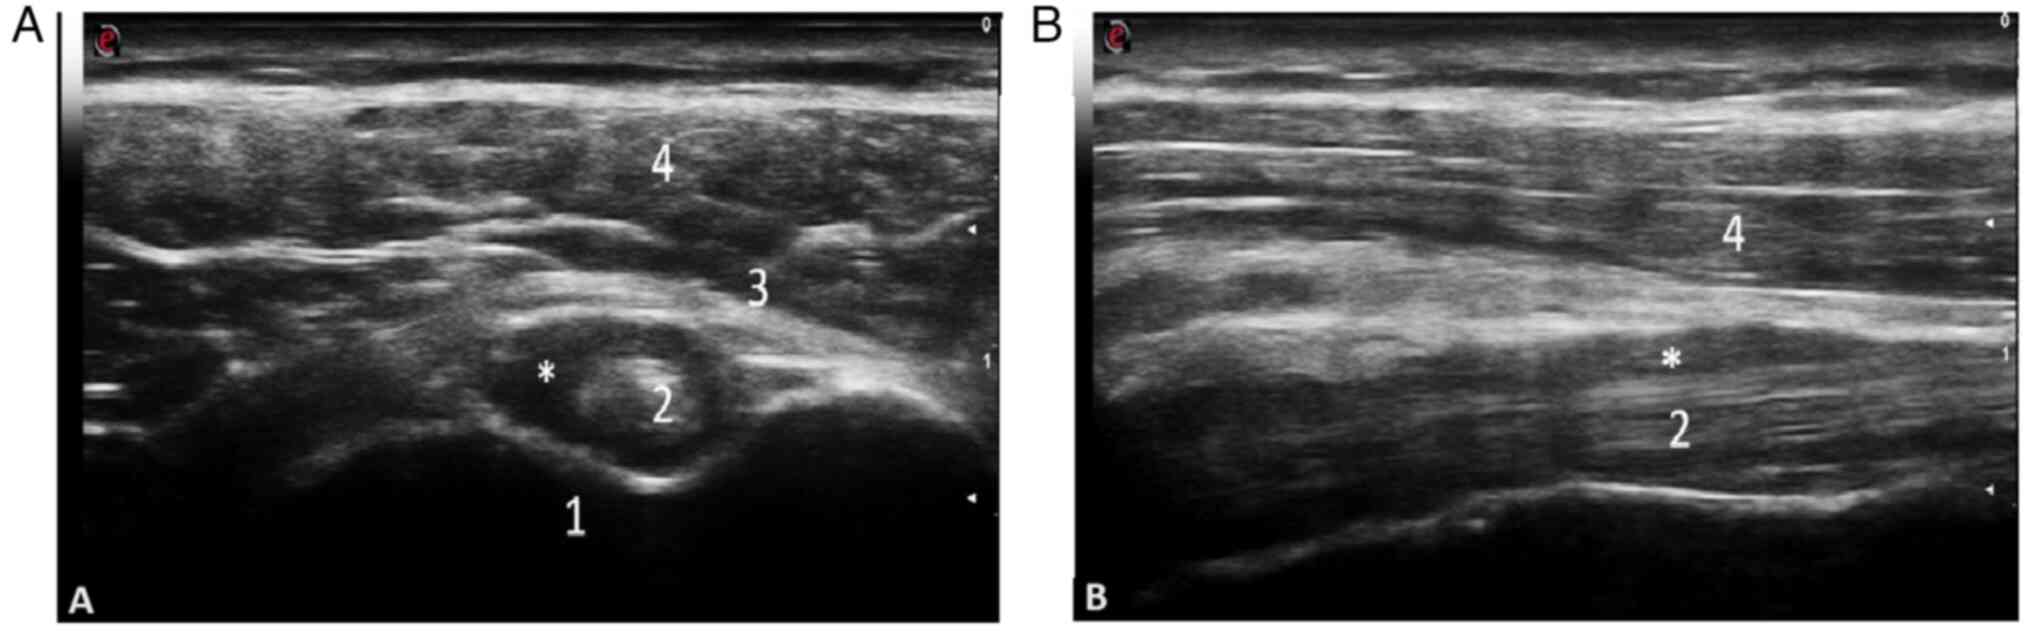

Diagnostic accuracy. As a result of several ultrasound studies performed in Europe, with regard to the detection of inflammatory lesions in PMR mostly using B-mode, and to a lesser extent, power Doppler examination, the most frequent ultrasound abnormalities described are bursitis of the subacromial/subdeltoid (SASD) bursae and tenosynovitis of the long head of the biceps tendon (LHBT), ranging from 6.2 to 100% at the shoulder level, with a higher prevalence of SASD bursitis, and less frequently, trochanteric bursitis and synovitis at the hip level (49,50). The importance of this data determined the inclusion of an ultrasound criteria for the first time in rheumatology in the 2012 EULAR/ACR Provisional Classification Criteria for PMR, increasing the specificity of the clinical diagnosis to 81% (51). Subsequently, Macchioni et al (52) revealed that the addition of ultrasound to clinical criteria increased the diagnostic performance from 81.5 to 91.3% in patients with PMR, while comparing PMR to other types of inflammatory arthritis, including RA. The diagnostic specificity in this case increased from 79.9 to 89.9% (Figs. 2 and 3). The images were obtained by examining a patient with PMR at the Emergency Clinical County Hospital of Craiova.

Transverse (A) and longitudinal (B) scan in gray scale of the long head of the biceps tendon illustrating a hypo/anechoic collection at the level of the long head of the biceps tendon in a 79-year old male patient (performed on a MyLabSix Ultrasound machine; Esaote SpA). 1, humerus; 2, long head of the bicep brachialis tendon; 3, transverse humeral ligament; 4, deltoid muscle; *, hypo/anechoic collection.

Written informed consent was acquired from the patients associated with the images presented in Figs. 2 and 3.

Patient consent for publication